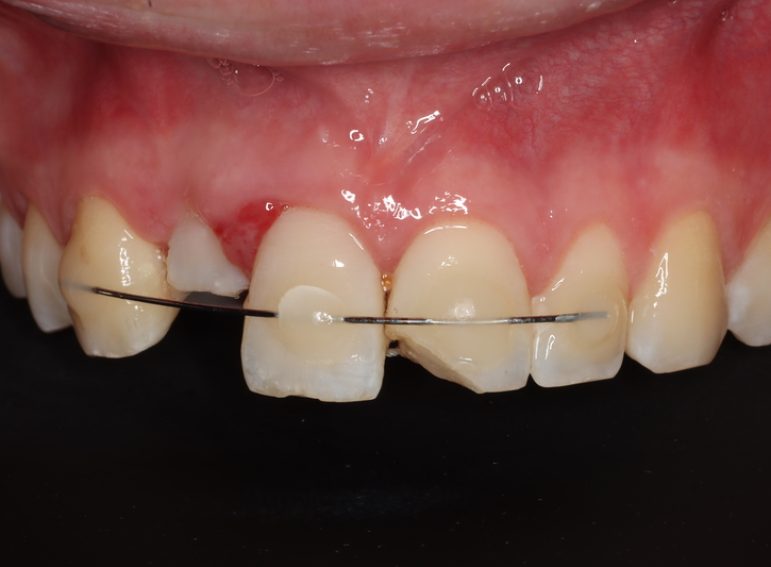

Surgical management of external cervical resorption.